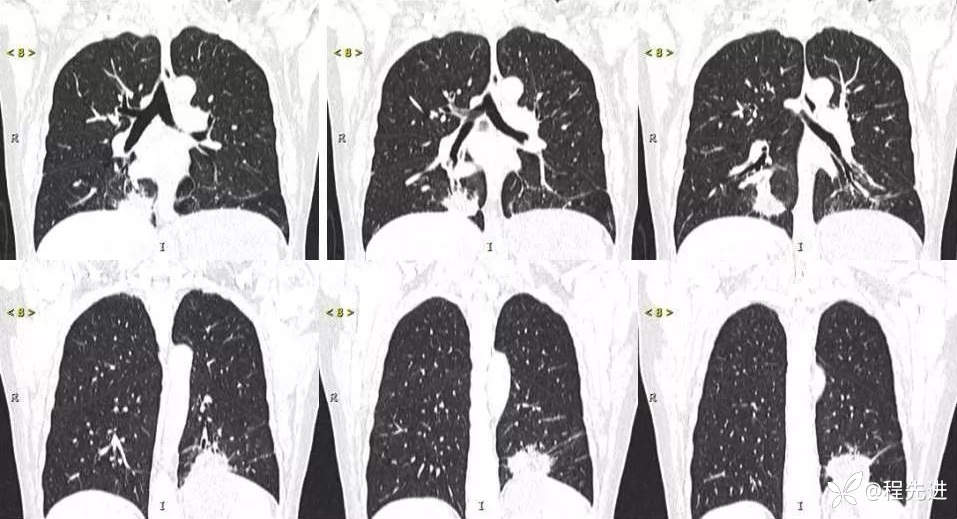

主诉:体检发现肺结节2周

现病史:患者2周前体检时发现两肺多发高密度影。无咳嗽、咳痰,无咯血、呼吸困难,无胸闷、胸痛,无发热、潮热盗汗。